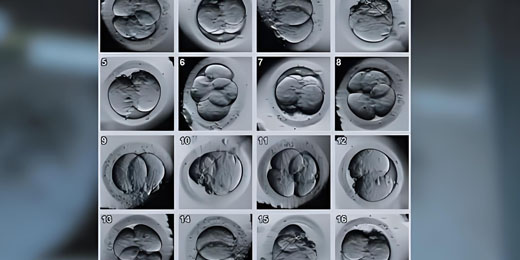

在辅助生殖技术不断发展的今天,三代试管婴儿技术为许多有生育需求的家庭带来了希望。对...